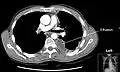

Chest computed tomography is more accurate for diagnosis and may be obtained to better characterize the presence, size, and characteristics of a pleural effusion. Lung ultrasound, nearly as accurate as CT and more accurate than chest X-ray, is increasingly being used at the point of care to diagnose pleural effusions, with the advantage that it is a safe, dynamic, and repeatable imaging modality.[15] To increase diagnostic accuracy of detection of pleural effusion sonographically, markers such as boomerang and VIP signs can be utilized.[16]

Massive pleural effusion, later proven to be hemothorax in a South Indian male.